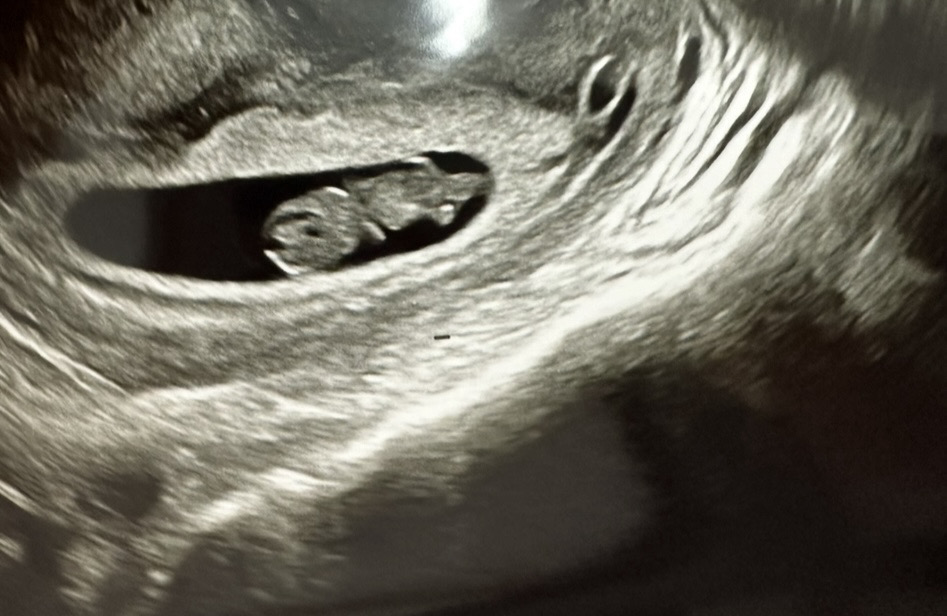

8주5일 젤리곰 보고왔어요!!

심장소리 들을때도 실감안났는데 저 젤리곰 보고 심장소리들으니까 신기하기도하고 대견 + 뭉클해서 눈물 두방울 흘렸네요 ㅋㅋ 꼼지락 움직이기도 하던데 너무 귀여워요 이 춈파사진으로 임밍아웃할거라 부모님들꺼 3장 뽑아왔어요ㅠㅠ♡